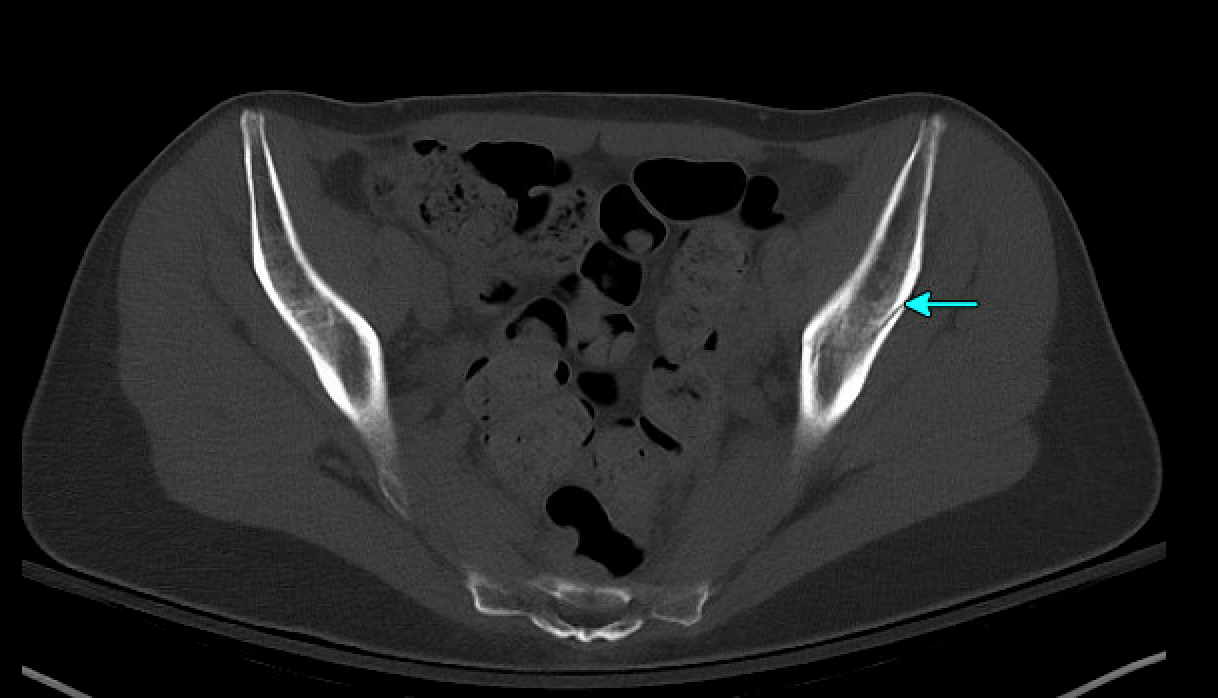

CT later confirmed fractures involving the left acetabulum and ilium, and bilateral pubic rami.